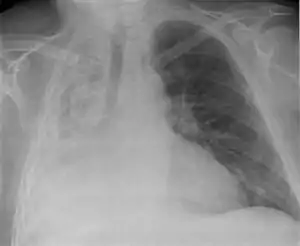

آتلکتازی (به انگلیسی: Atelectasis) یا شُشچسبیدگی فرواُفت شش، عبارت است از جمع شدن یک قسمت از ریه یا تمامی یک ریه. این وضعیت باعث عدم جذب اکسیژن به مقدار کافی از ریه میشود. دیدن آتلکتازی در رادیوگرافی قفسه سینه شایع است.

در معاینه فیزیکی اگر ناحیه آتلکتازی وسیع باشد ما در آن ناحیه ماتیته در دق و کاهش صداهای تنفسی در سمع داریم. تشخیص بالینی با روشهای پاراکلینیک مانند رادیوگرافی قفسه سینه (chest x-rays) برونکوسکوپی و سی تی اسکن تأیید میشود.